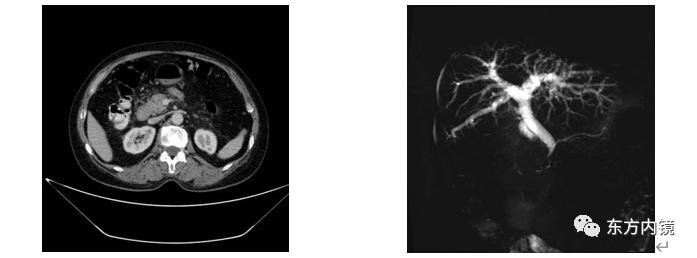

医院给她查了肝功能发现胆红素比正常升高了好几倍(85.5umol/L),肿瘤标志物CA-199明显升高(331.3ng/ml),进一步做CT发现胰腺头部略增大,隐约有异常回声占位,磁共振(MRCP)发现胆总管已经有轻度扩张。

(CT及MRCP)为了明确诊断,给江阿姨做了超声内镜,在胰腺头部发现了一个2-3cm的低回声占位,超声穿刺明确诊断为胰腺癌。

(4)增强CT检查:是目前检查胰腺最佳的无创性影像检查方法,主要用于胰腺癌的诊断和分期。

(5)增强磁共振及磁共振胰胆管成像(MRCP)检查:安全性高,但不作为诊断胰腺癌的首选方法,MRCP对胆道有无梗阻及梗阻部位、梗阻原因具有明显优势。